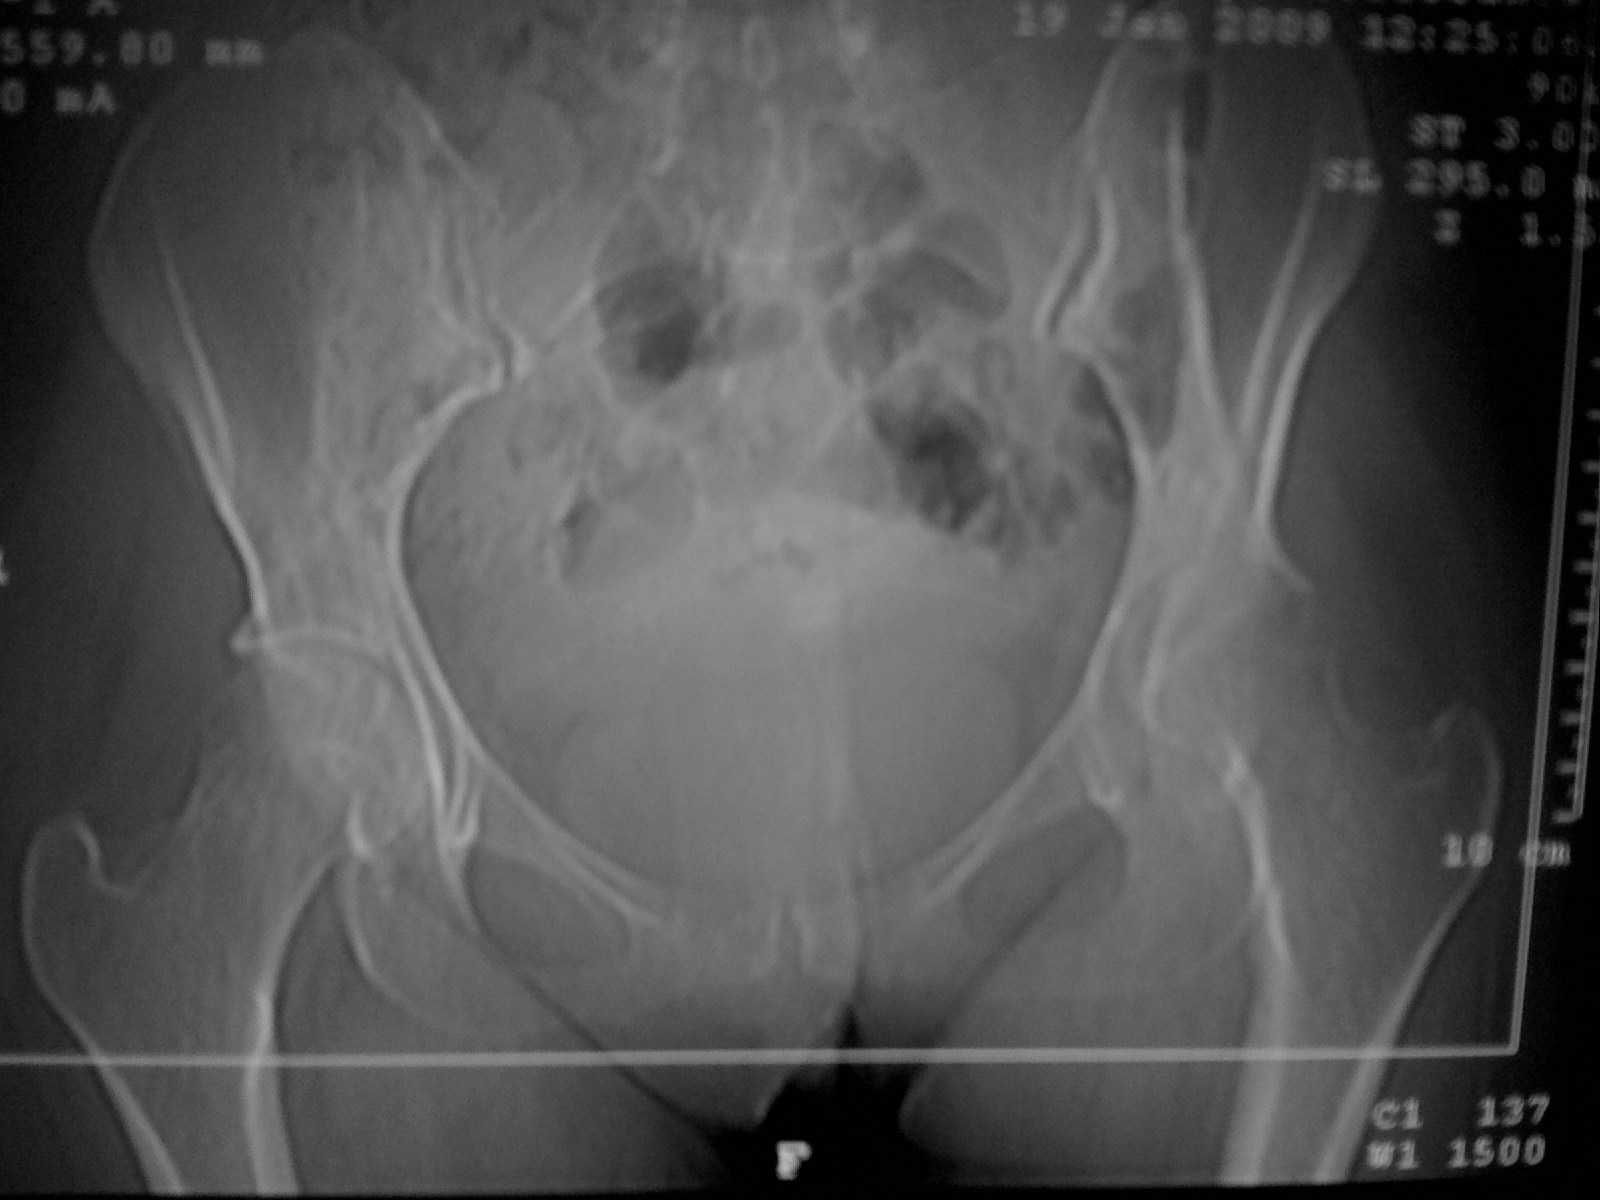

Коллеги! Пациентки 27 лет. Впервые обратилась 6 мес.назад после родов расхождение лонного

сочленения, проведена консервативно. Через 3 мес.повторное обращение по поводу болей в т\б

суставе.Ходит с костылями, отведение, приведение в суставе в пределах 10*.Укорочение

н\конечности на 3,0см.Непонятен механизм развития данной ситуации и какой метод лечения

выбрать. Если протез то какой?